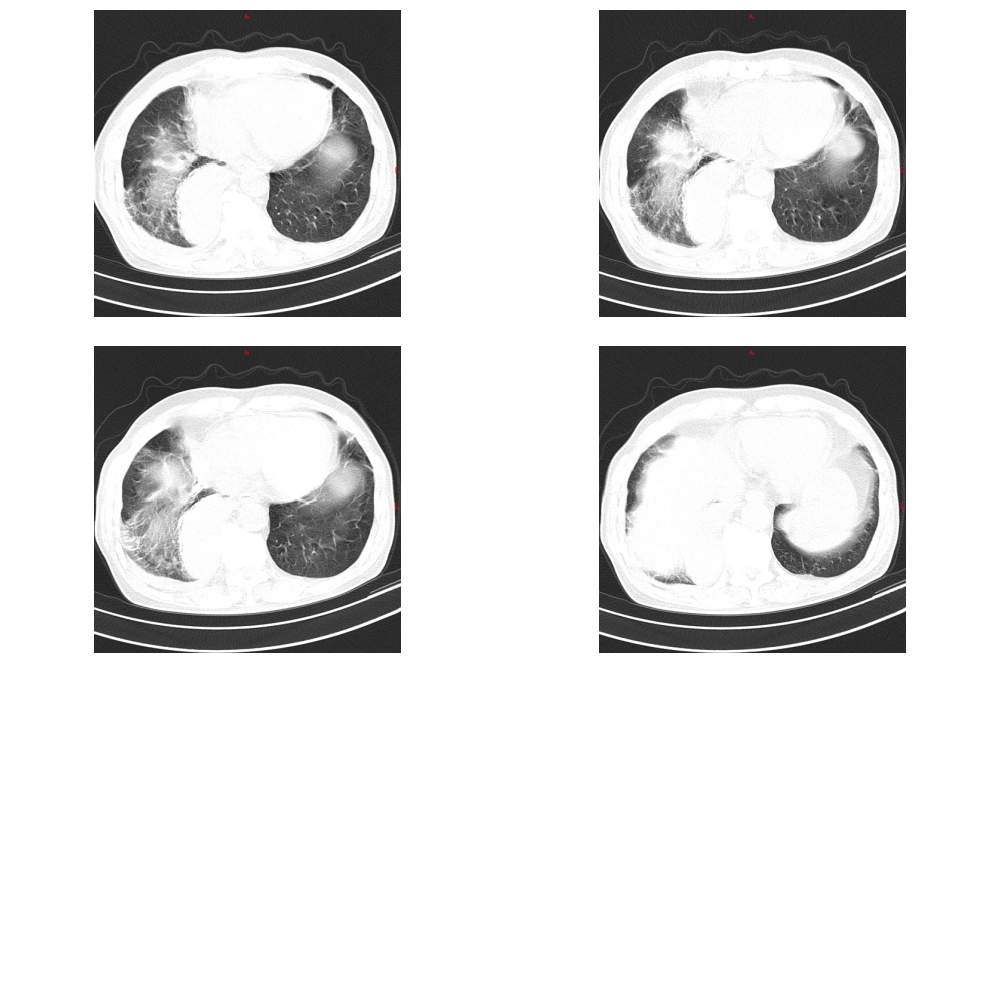

以下是引用余辉在2007-5-21 17:54:00的发言:[br]考虑右下叶中央型肺癌左上舌段转移,右下叶阻塞性肺气肿,右侧胸腔积液,建议增强与肺隔离症等鉴别

以下是引用苯小孩在2007-5-22 11:28:00的发言:[br]1、右肺下叶中心型肺癌可能性大<肺叶有不张,斜裂后移>,右侧胸腔积液,建议纤支镜活检.2、左肺舌叶陈旧性病灶/转移?

以下是引用lihongwei在2007-5-22 9:33:00的发言:[br]以下是引用liuyue [br]在2007-5-22 7:28:00的发言:[br]1右下肺片状影,考虑:右下肺肺炎;[br]2右下肺野脊柱旁宽带状影,边缘较清,其前端可见条索影似与降主动脉相连,考虑1)肺隔离症可能性大(2)包裹性积液?(3)肺癌待除外.[br]3左上肺舌段钙化灶[br]4降主动脉前侧块状影,考虑:食管病变可能性大,[br]5肝上缘突凹不平,-----肝硬化?

以下是引用老爱克斯新网客在2007-5-22 17:55:00的发言:[br]右肺下叶后基底段块状病灶,支气管闭塞,斜裂下段向后移位(说明有肺不张),考虑中心型肺癌,